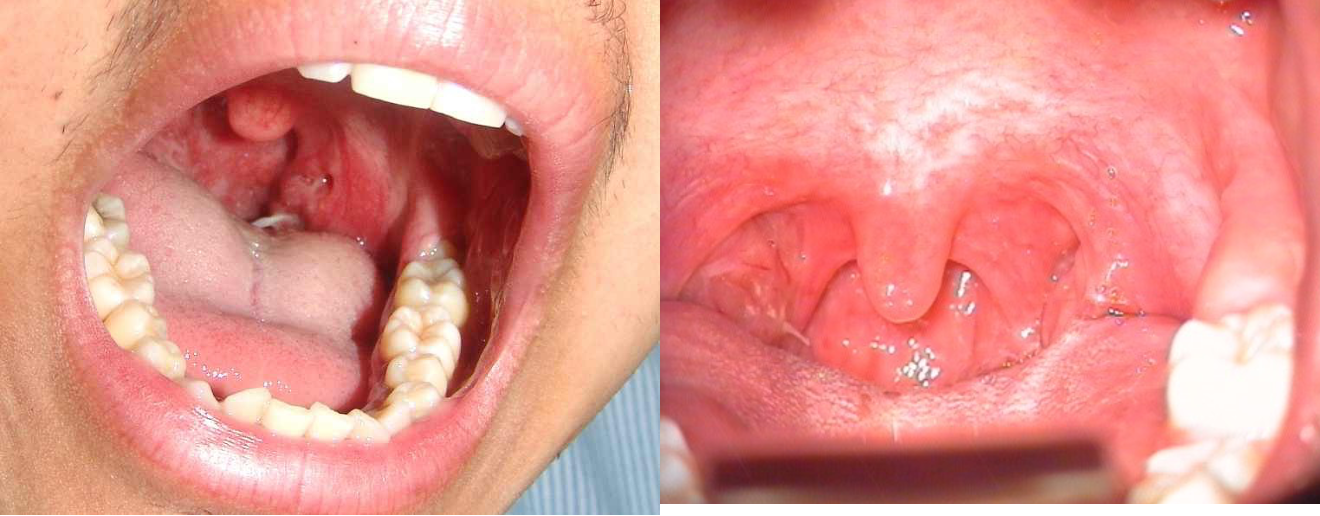

Pharynx Foreign Bodies

- Usually sharp FB

- Fish bone is the most common

- Common sites: tonsils, base of tongue, and vallecula

- Diagnosis by physical examination

- Treatment by removal